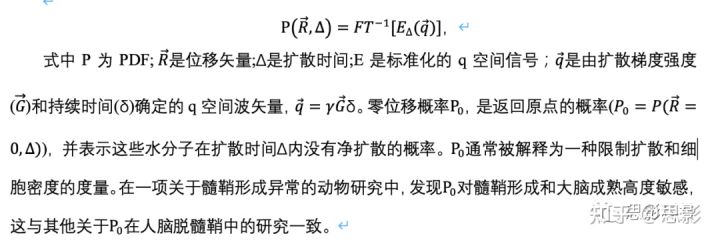

表1 白质ROIs,它们的首字母缩写,以及体素数量的大小。体素定义在标准MNI空间中,具有1毫米的各向同性分辨率。首字母缩略词的颜色与图2所示的ROIs相匹配。

本研究考虑了白质中的48个感兴趣区域(ROIs),包括相同解剖结构的双侧区域(图1)。在标准MNI空间中定义ROIs,并将所有扩散度量图都非线性转换到标准空间进行统计分析。使用FSL配准工具FLIRT和FNIRT将个体受试者的FA map非线性地配准到标准空间FA图像(FMRIB58_FA_1mm)上。将相同的变换矩阵应用于其他扩散度量。为了避免灰质和脑脊液的部分体积效应,通过将白质图谱、Johns Hopkins University(JHU)ICBM-DTI-81与所有受试者创建的共同白质骨架相交叉,白质ROIs具有高度选择性(图1)。JHU的白质图谱是在FSL中提供的,而白质骨架是使用FSL在其基于纤维束示踪的空间统计(TBSS)工具箱中提供的命令创建。ROIs和体素数的定义如表1所示。

图1 通过将平均FA骨架和白质图谱相交,在标准MNI空间中定义了48个白质ROIs。

平均FA骨架由47名受试者的TBSS命令创建,白质图谱由FSL的JHU ICBM-DTI-81提供。下图显示了标准MNI空间中覆盖在平均FA图上的48个ROIs。表1中列出了ROIs的首字母缩写词,并带有匹配的颜色。